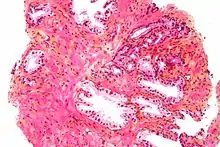

Micrograph showing an inflamed prostate gland, found in prostatitis. A large amount of darker cells, representing leukocytes, can be seen. An area without inflammation is seen on the left of the image. H&E stain.

Prostatitis is inflammation of the prostate gland. It can be caused by infection with bacteria, or other noninfective causes. Inflammation of the prostate can cause painful urination or ejaculation, groin pain, difficulty passing urine, or constitutional symptoms such as fever or tiredness.[27] When inflamed, the prostate becomes enlarged and is tender when touched during digital rectal examination. The bacteria responsible for the infection may be detected by a urine culture.[27]